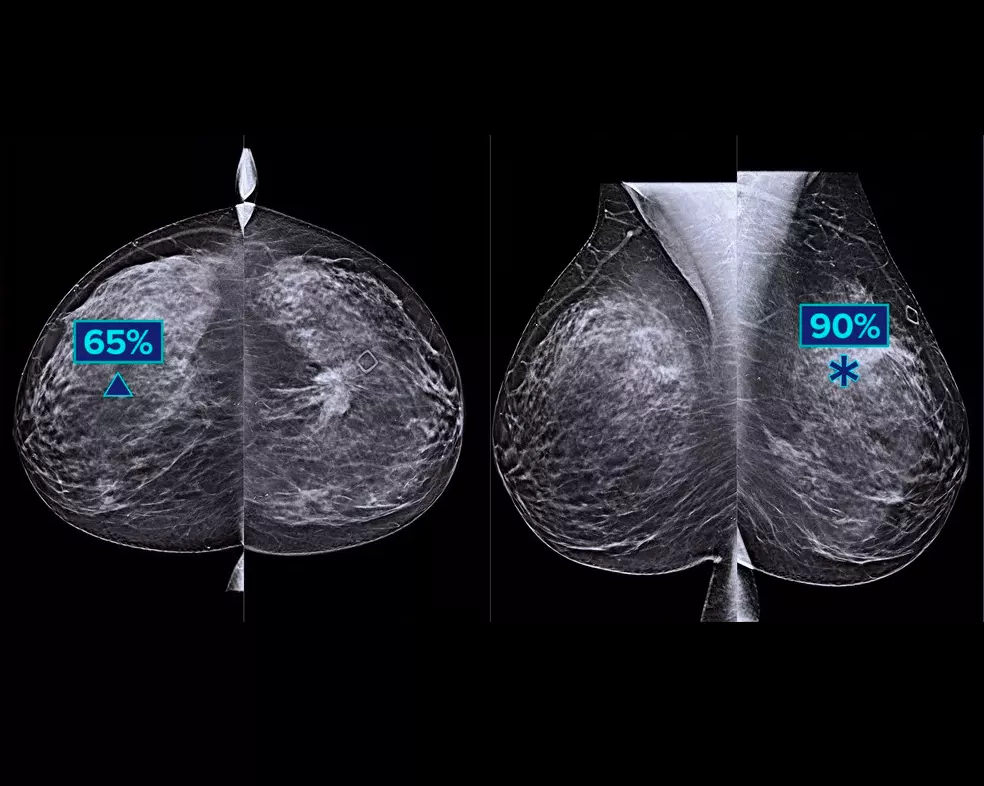

A machine-learning algorithm designed to aid radiologists' diagnostic performance in detecting breast cancer1-3 from tomosynthesis images obtained by using the Hologic Dimensions™ Mammography Systems. The algorithm locates lesions that are likely to represent breast cancer by searching each slice of the tomosynthesis image set. The suspicious areas are highlighted for concurrent reading at the radiologist's workstation to aid in interpretation.

The algorithm looks for 3 main groups of suspicious lesions: calcifications, masses, densities and distortions, and any combination of these lesions. Outputs may vary on different reading workstations.

Integration on the acquisition workstation allows flagging of high-risk cases for immediate reading. Provides case-level metrics, helping categorise cases for priority reading.